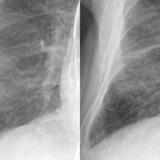

peribronchial cuffing

peribronchial cuffing bef and after

Date: 01/06/2018

Views: 6998